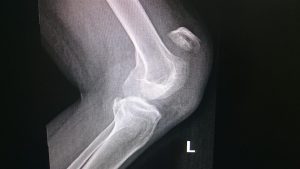

Figure 3 demonstrates a fluid filled bursa over the ligament and distal patella. On this fat suppressed image, the bursa manifests high signal intensity (white), due to the relatively pure fluid content.

Figure 3